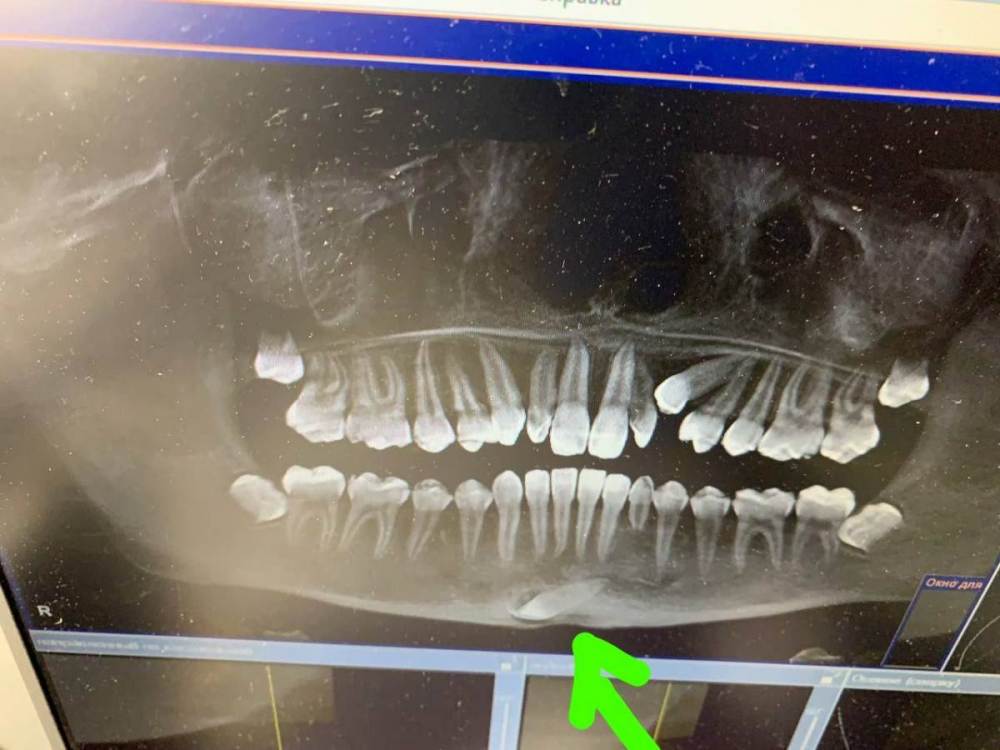

vakalo.anastasia Опубликовано 18 февраля, 2023 Поделиться Опубликовано 18 февраля, 2023 Подростку 14 лет. Поздняя смена молочных зубов. Сделав снимок обнаружен ретинированный зуб, точнее со слов врача в этом месте два ретинированный зуба (один нижний клык и один внекомплектнный). Вопросов много... Надо ли операция по их удалению? Какая угроза для челюсти и зубов если все так оставить? Ссылка на комментарий

Irouil Опубликовано 18 февраля, 2023 Поделиться Опубликовано 18 февраля, 2023 Сверхкомплектного не вижу. Судя по этому снимку - показана ортодонтия, ортодонт может настоять на удалении ретинированных зубов мудрости. Клык на нижней челюсти с большой долей вероятности трогать не нужно, но надо бы ещё КТ срезы посмотреть для пущей уверенности 1 1 Ссылка на комментарий

vakalo.anastasia Опубликовано 18 февраля, 2023 Автор Поделиться Опубликовано 18 февраля, 2023 Спасибо за ответы. Знаний ещё мало. Сделан панорамный снимок и КТ. И на КТ врач определила что там именно два зуба. Хотя я не вижу. Начиталась про удаление. Про риски. Очень не хочется втягивать в это ребенка. Пока хирург сказала остро вопрос удаления если есть киста или воспаление. В этой части вроде в норме. Пугает не мешает такой лежачий зуб корням передних центральных зубов? на снимке вижу что они немного выше. И про зубы мудрости тоже поняла что без удаления сами не вылезут. Ссылка на комментарий

Irouil Опубликовано 18 февраля, 2023 Поделиться Опубликовано 18 февраля, 2023 В 14 лет говорить о самостоятельном прорезывании зубов мудрости ещё рано. Лежачий зуб корням зубов не мешает. Ссылка на комментарий